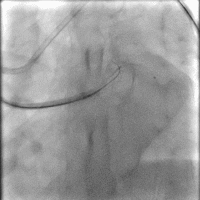

Figure 1

前降支CTO 无残端齐头闭塞

右冠急性闭塞